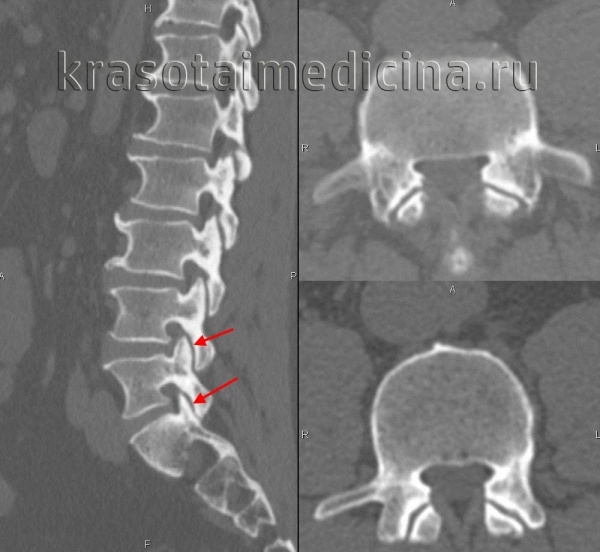

КТ поясничного отдела позвоночника. Деформирующий спондилоартроз. Умеренно выраженные дегенеративные изменения дугоотростчатых суставов